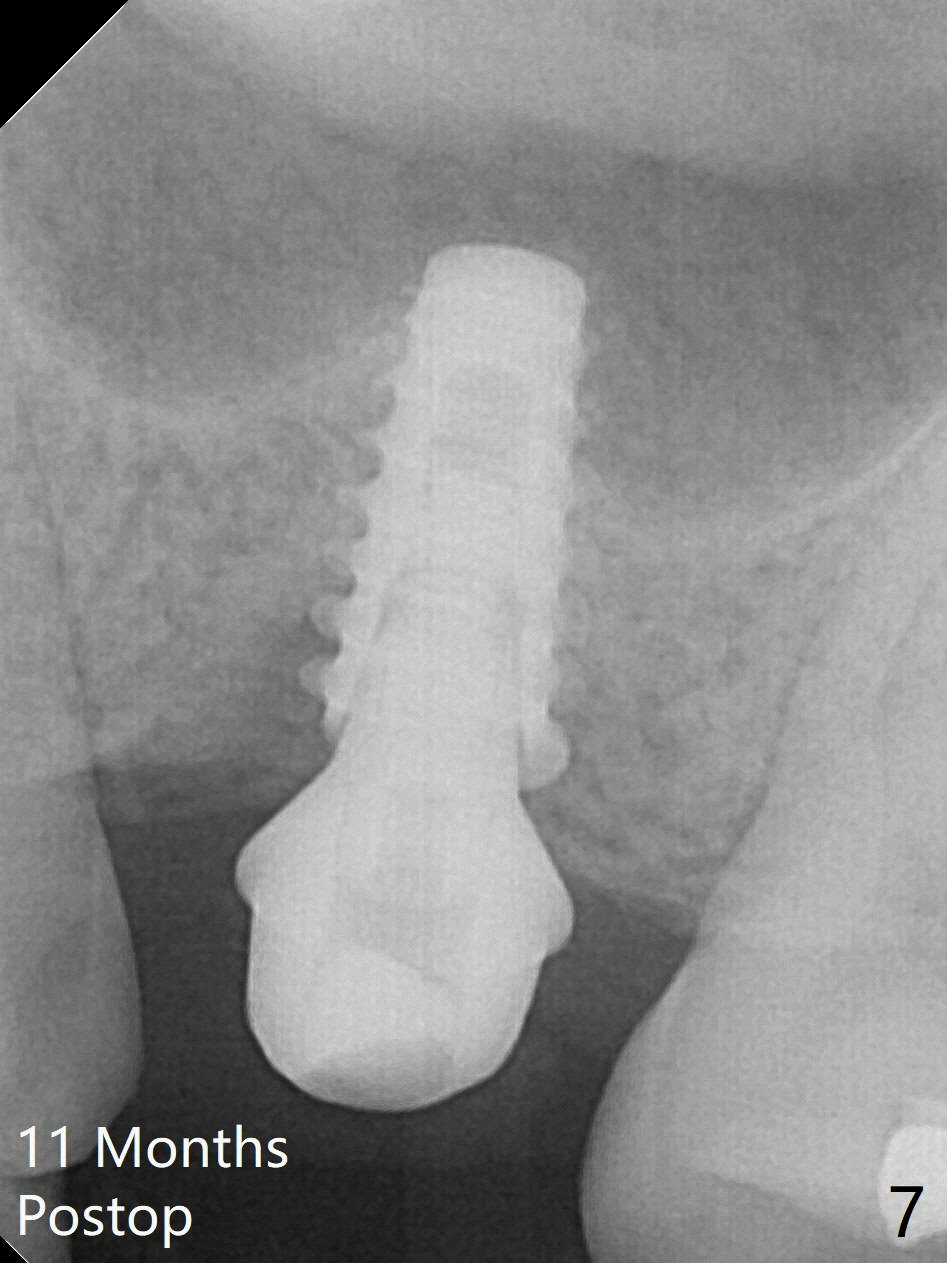

While the base of the ridge at #14 is wide, the top is moderate. IBS Magic Split is applied to gain access and test bone density (flapless). In fact the bone is hard. A 1.6 mm pilot drill is used for 9 mm (gingival level), followed by insertion of a parallel pin (Fig.1). Following Magic Expander 3.0 mm and Magic Drill 3.8 mm for ~ 11 mm (with empty feeling without air leak), a 4x11 mm dummy implant is placed with 25 Ncm (Fig.2). After insertion of a 4.5x11 mm dummy implant at 9 mm (35 Ncm; for further bone expansion), one piece of PRF plug and 1 piece of PRF membrane are pushed into the osteotomy, followed by allograft mixed with autogenous bone for sinus lift and placement of a 5x9 mm implant (Fig.3,4 with insertion torque >50 Ncm). A 6x4(2) mm abutment is placed for fabrication of an immediate provisional (Fig.5 P). There is no nasal hemorrhage postop. PRF membrane and plug are used to prevent and repair sinus membrane perforation and facilitate wound healing. There is mild bone resorption at the crest 11 months postop (Fig.6,7). The bone resorption seems to be worse 8 months post cementation (Fig.8,9); in fact the abutment screw is loose.